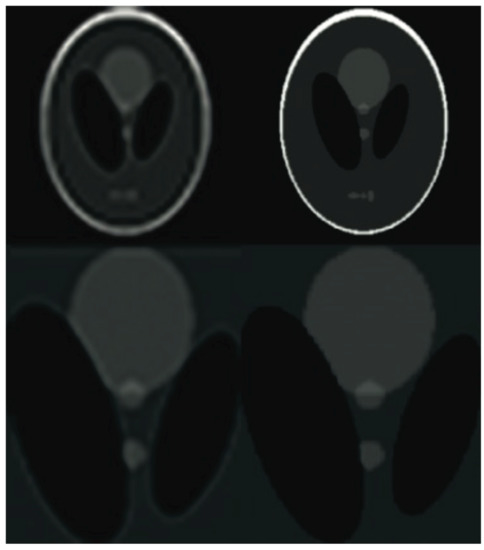

Figure 9. The Shepp-Logan phantom results comparison. From the left: the PROPELLER sampling reconstruction output (PSNR = 29.84 dB, IEM = 2.04), the proposed algorithm result with enhanced resolution (PSNR = 34.58 dB, IEM = 3.64). The lower row shows detailed images. Please see Table 4 for the PSNR values at other compression ratios.